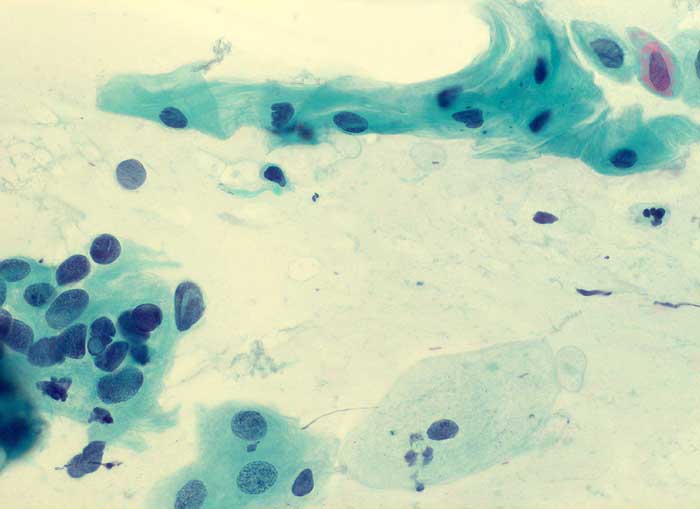

PathoPic – image database / PathoPic ID 6113 - ASCUS

ASCUS

Zervix

Zervixabstrich: hoher Epithelaufbau. Nicht sicher klassifizierbare Plattenepithelien mit vergrösserten hyperchromatischen Kernen und mittelbreitem Zytoplasmasaum.

Keine histologische Untersuchung. Weitere zytologische Kontrollen unverdächtig.

400